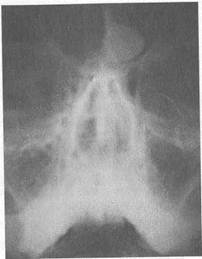

Остеома. Доброкачественная опухоль, исходящая из костной ткани и отличающаяся медленным ростом (рис. 7.1). Чаще располагается в лобных пазухах и в решетчатой кости, реже — в верхнечелюстных пазухах.

Остеомы маленьких размеров часто остаются незамеченными и обнаруживаются случайно на рентгенофамме околоно-

совых пазух. При отсутствии функциональных, косметических и иных нарушений нет оснований к немедленному хирургическому лечению остеомы. В таком случае проводят длительное наблюдение; заметный рост остеомы является показанием к ее удалению. Следует отметить, что иногда маленькие остеомы, особенно на церебральной стенке лобной пазухи, являются причиной упорной головной боли. После исключения других причин головной боли показано удаление такой остеомы. Иногда остеомы достигают больших размеров, могут распространяться в полость черепа, в глазницу, деформировать лицевой скелет и являться причиной мозговых расстройств, головной боли, понижения зрения, нарушения носового дыхания и обоняния. Лечение хирургическое. Остеомы средних и больших размеров даже при отсутствии тяжелых симптомов подлежат полному удалению.